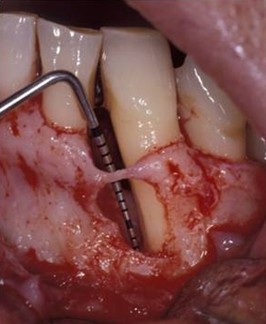

一見、問題のない歯茎に見えますが、器具が歯と歯茎の間に深く入ります。

レントゲン写真では、骨の吸収が予測できます。

実際に、歯茎を開いてみると、大きく骨が減っているのが確認できます。